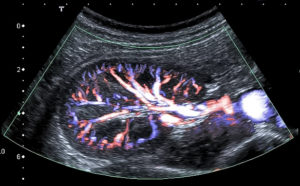

Цветовое разрешение показателей, иначе цветовое допплеровское картирование (ЦДК) имеет большую информативность, поскольку, фактически, исключает ошибки при диагностике. Красным цветом на мониторе отображается кровоток, направленный к датчику, голубым – движение кровотока от датчика. Яркость цвета определяется скоростью процесса тока крови.

ЦДК, как вид УЗИ, основанный на Допплеровском эффекте, позволяет оценить сосудистый кровоток. Основой ЦДК является сочетание черно-белого изображения в УЗИ-диапазоне и оценки тока крови по допплеру.

Когда аппарат установлен в режим ЦДК, врач может видеть на мониторе обычное УЗ-изображение. В той его части, которая изучается, в цвете даны скорости потока крови.

Способы цветной кодировки картограммы следующие:

- оттенками красного цвета кодируют скорость кровотока, движущегося по направлению к датчику;

- оттенками голубого – скорость тока крови, движущейся от датчика.

Цветное допплеровское картирование дает врачу возможность максимально точно рассмотреть характеристики кровотока в почечных сосудах, с использованием цвета

Чем менее насыщенный цвет, тем, соответственно, меньше скорость. Кроме того, на мониторе отображена оттеночная шкала и ее расшифровка (описание соответствия оттенка-скорости).

ЦДК визуально отображает и анализирует: направление, скорость и характер потока крови, проходимость, сопротивление и диаметр изучаемого сосуда.